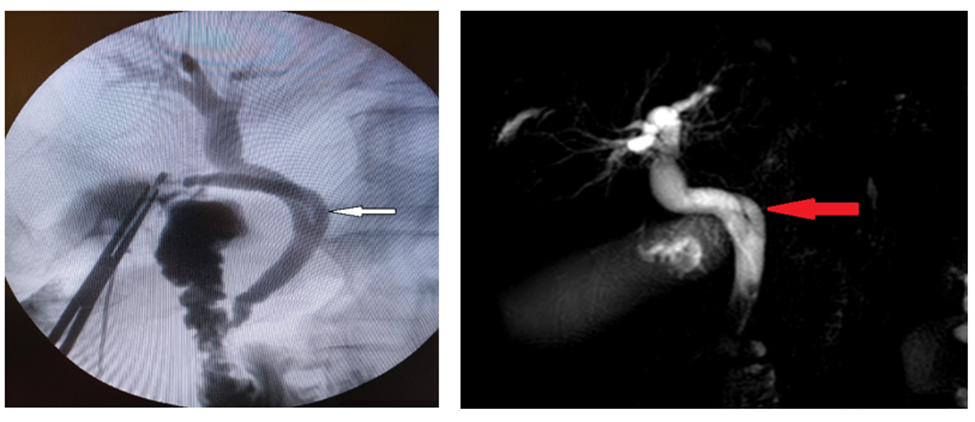

Before the end of the operation, intraoperative cholangiogram was performed through the cystic duct, which showed in the affirmative spiral course of cystic duct with medial insertion with CHD, intact CBD, CHD, as well as right and left hepatic ducts without stones (Figure 2).

Figure 2: Intraoperative cholangiogram shows spiral course of cystic duct (white arrow) with medial insertion with CHD.